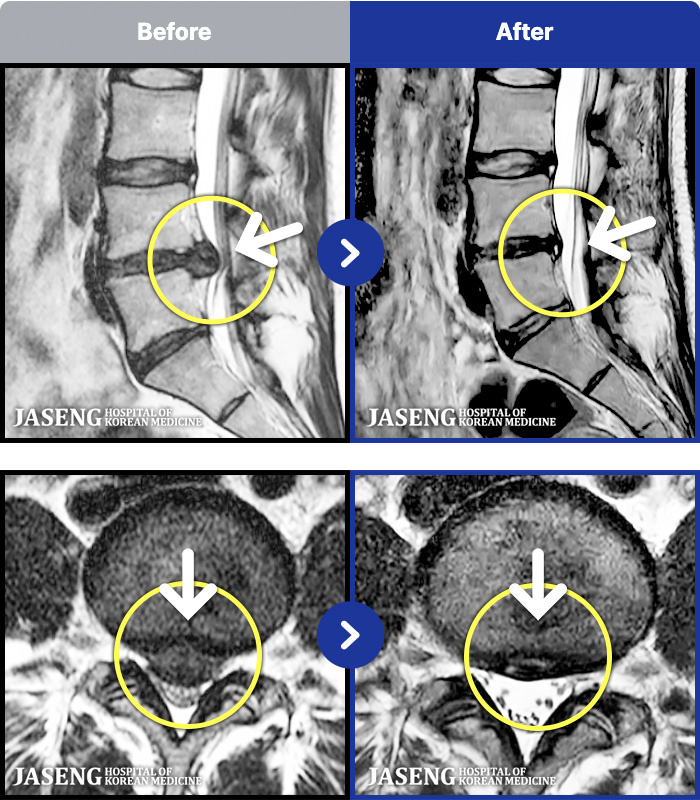

- MRI ġ

MRI ġ

1,299 MRI ũ ʸ Ȯϼ.